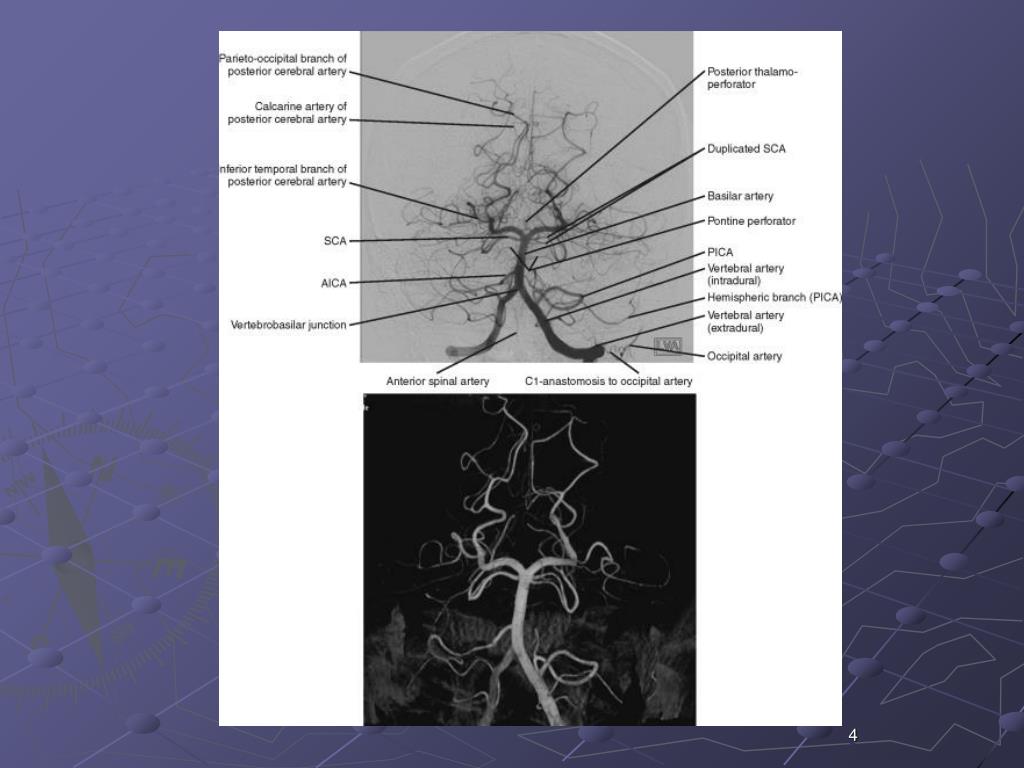

6. 4